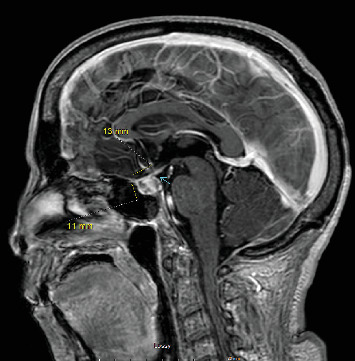

Abstract Image

Immune checkpoint inhibitors have revolutionized cancer treatment, yet their use is associated with unique and sometimes unpredictable immune-related adverse events. We present a case of a 67-year-old female with renal cell cancer treated with ipilimumab and nivolumab who developed aseptic meningitis and hypophysitis. This case highlights the challenges in managing immune-related adverse events and underscores the need for vigilance in monitoring patients receiving ICIs.